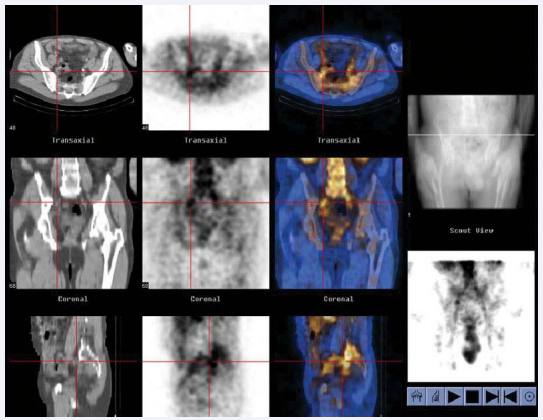

Positron emission tomography scans: Positron emission tomography (PET) is a scan that uses a form of radioactive sugar. Body cells take in different amounts of the radioactive sugar, depending on how fast they are growing. Cancer cells, which grow quickly, are more likely to take up larger amounts of the sugar than normal cells. The radioactive sugar gives off tiny atomic particles called positrons, which run into electrons in the body, giving off gamma rays. A special camera picks up these rays as they leave the body and turns them into pictures.

PET scans are used to find cancer and to see if it’s responding to treatment. The chemical changes they show can also help doctors look at the effects of cancer treatment. Because PET scans look at body function, they may show changes that suggest disease before the changes can be seen on other imaging tests.

PET/CT scans: Some machines combine a PET scan with a CT scan. PET/CT scanners give more detailed information on any increased cell activity, helping doctors pinpoint tumors. But they also expose the patient to more radiation.